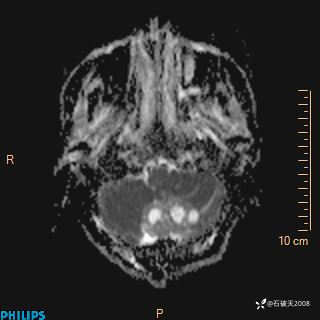

DWI

ADC